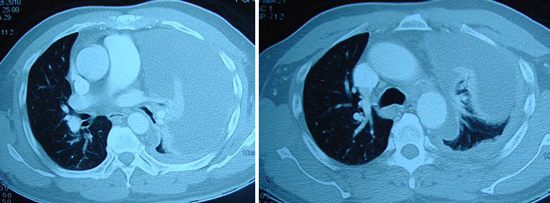

Jane (not real name) was a 47-year old lady from South Africa. She lived with her husband and their dog in a boat that sailed around the world. The happy family had been sailing like this for the past 15 years. Sometime in mid-2013, they landed in Malaysia. Jane developed breathing difficulty and was subsequently diagnosed with lung cancer. CT scan showed a 3.2 x 4.1 x 6.7 cm mass in her lung.

Bak (M952) is a 56-year-old male from Indonesia. Sometime in November 2010, he complained of itchiness but he did nothing about it. In April 2011, he went for a checkup in a hospital in Aceh, North Sumatera. He was told there was a tumour in his bile duct. On 8 April 2011, he came to Penang for further checkup. CT scan of his abdomen and pelvis indicated the following:

Bob was a 57-year-old male. In early 2010 he went to a government hospital complaining of shortness of breath. Examination indicated irregular hard swelling below the costal margin (liver area). He was jaundiced. A CT scan on 19 April 2010 indicated multiple nodules of varying sizes in both lung fields suggestive of metastases. Soft tissue nodules at the hilum – right measures 1.4 x 1.4 cm, left measures 2.3 x 2.7 cm. Enlarged liver with a 9.9 x 10.5 cm lesion in the right lobe. Multiple lesions present in both lobes of the liver. These may represent metastases.

Sujo (M858) is a 58-year-old male from Indonesia. Sometime in August 2010, he complained of breathlessness when climbing the stairs. A check up with a GP in Medan indicated fluid in his lungs.  Sujo came to a private hospital in Penang in October 2010. A CT scan indicated gross left pleural effusion associated with severe lung collapse. There was lytic lesion at T4 vertebral body associated with erosion. His liver showed fatty infiltration.